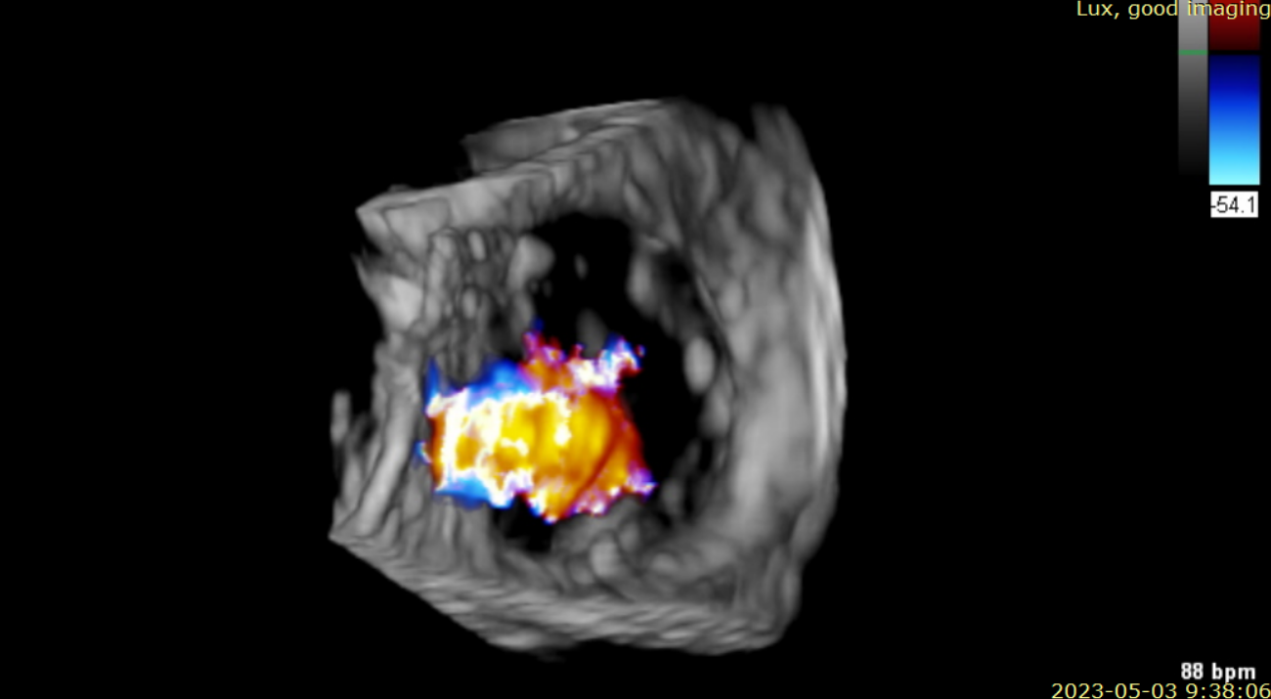

術后超聲提示無瓣周漏

術后超聲提示僅殘余輕微瓣周漏

術后Azeem Latib教授對LuX-Valve Plus經血管三尖瓣置換系統的器械性能和治療效果大為稱贊,并且認為LuX-Valve Plus的手術體驗非常好。從治療效果來看,術后即刻超聲顯示三尖瓣反流幾乎完全消失,血流動力學改善顯著,患者恢復快。在面對復雜解剖結構、超聲影像質量不佳、有起搏導線干擾時,Lux-Valve Plus也體現了極強的適應性。Thomas Modine教授參與了術中指導,他同樣再次肯定了LuX-Valve Plus術中操作的便捷性,認為LuX-Valve Plus容錯率高,對術中影像的依賴小,并表達了后期希望可以更多地應用LuX-Valve Plus三尖瓣置換系統于臨床實踐,讓更多的三尖瓣重度反流患者盡早獲益,改善預后。